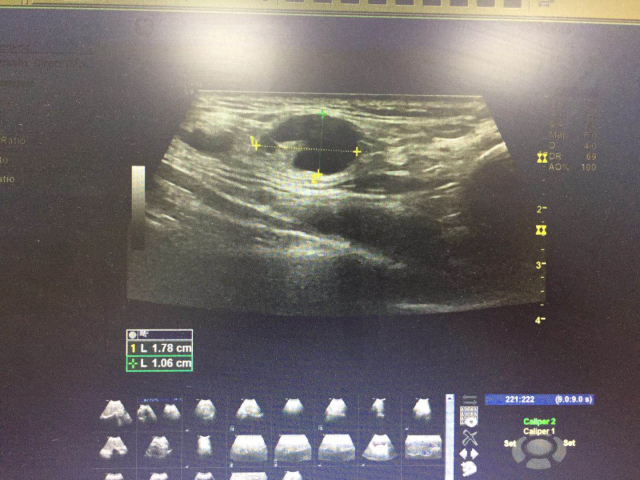

查乳腺、腋下、锁骨上彩超显示:

1. 右侧腋下低回声结节,考虑:淋巴结?

2. 左侧锁骨上多发低回声包块(左侧锁骨上可见多个低回声包块,较大的约 1.8×1.1cm,边界清,外形规则,CDFI:未见明显血流信号)

乳腺彩超显示:

1. 右侧腋下低回声结节,考虑:肿大淋巴结?

2. 左侧锁骨上多发低回声结节,请结合临床及其他检查,建议复查。